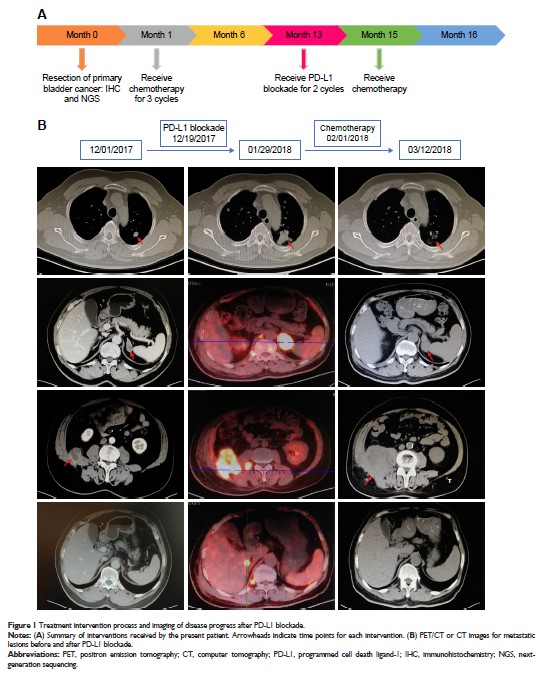

Case Report

- 作者:Wen Jiang, Jiali Xu, Rong Wang, Tingting Wang, Yongqian Shu, Lianke Liu

- 期刊:OncoTargets and Therapy